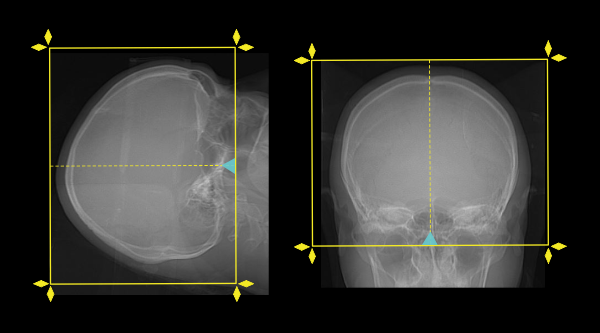

Scan planning

- Plan the scout start point (laser indicator) at the upper lip of the patient.

- Plan the scan slab from the skull vertex to skull base for both pre- and post-contrast scans.